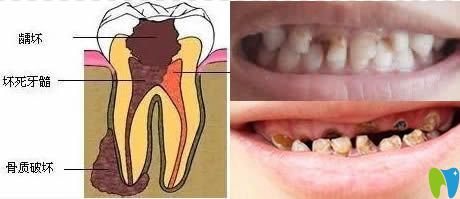

我們通過(guò)下圖來(lái)看看齲齒發(fā)展速度有多快?

齲齒發(fā)展過(guò)程圖解

1、先是齲壞于牙釉質(zhì)層;2、發(fā)展到牙本質(zhì),這時(shí)已對(duì)冷熱刺激感到敏感;3、牙髓炎階段,開(kāi)始自發(fā)陣痛;4、由牙髓感染導(dǎo)致根尖發(fā)炎疼痛,面部腫脹;5、牙冠破壞,根尖病變,牙頜骨質(zhì)開(kāi)始遭到破壞。